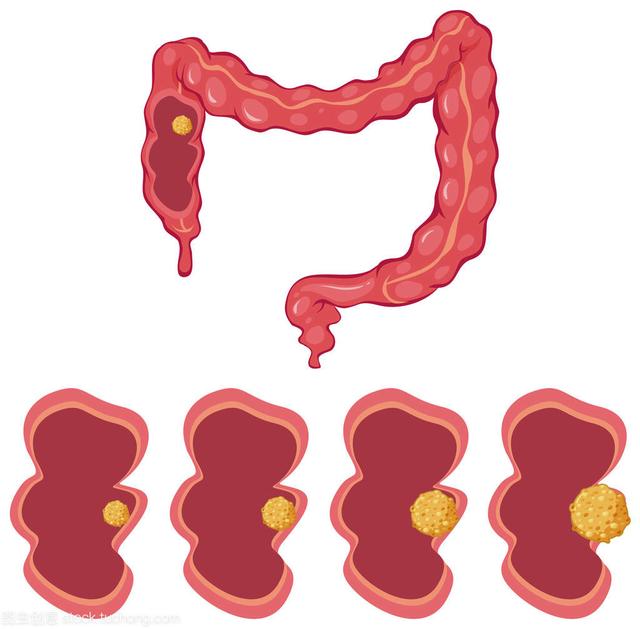

3.大腸がん

(1)大腸癌の発生率は、遺伝的要因、食習慣などに関係している。低繊維質、高蛋白食、揚げ物、焼き物などは危険因子であり、喫煙も大腸癌の危険因子である。腸癌の多くは腺腫から変化したものである。

(2) 大腸がんの症状には、腹痛、下痢、黒色便、便秘、排便習慣の変化、便の形質や形の変化、やせなどがある。

(3) 結腸癌と直腸癌のスクリーニングでは、大腸内視鏡検査が最も重要な検査である。肛門から直腸に入り、直腸、S状結腸、下行結腸、横行結腸、上行結腸と続き、腸がんがないか、見ればわかるが、その前提は腸が十分に準備されていることで、そうでなければすべての便がはっきり見えない。

(4) 大腸がん

男女を問わないが、50歳以上で、大腸がんの家族歴があり、下腹部の痛みが頻繁にあり、慢性大腸炎があり、排便回数が多く、便に血液や粘液が混じる人。従うべきである:大腸内視鏡検査、便潜血検査(年1回実施)。

腫瘍マーカーCEA、CA-199、CA242。

(3)大腸ポリープのある人、腸炎のある人、長期間アルコールをたくさん飲む人、漬物を好んで食べる人。40歳以上は3~5年ごとに大腸内視鏡検査を受けることが推奨されている。

検診の焦点:腸がん

経験:大腸内視鏡検査

便に血が混じっていることに気づいたら、痔だと思わずに医師に相談し、必要であれば大腸内視鏡検査を受けること。